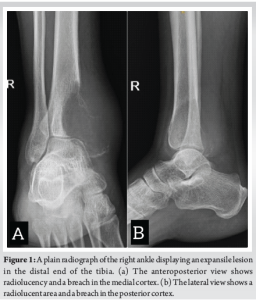

A 36-year-old male presented after noticing a gradually increasing swelling over his right ankle for the past 3 months. It was associated with a dull and diffuse type of pain which was aggravated with weight bearing. He denied a history of any previous trauma. He had noticed significant weight loss in the past 6 months. On clinical examination, there was a localized swelling of size 5 × 3 cm over the medial aspect of the ankle, which was tender, immobile, with ill-defined edges, and was bony hard in consistency. The range of movements in the ankle was minimally restricted in comparison with the contralateral side. There was no neurovascular deficit in the affected limb. Plain radiographs of the affected limb were done and showed an ill-defined, radiolucent, expansile lesion in the medial aspect of the distal end of the tibia, with a posteromedial cortical breach and a narrow zone of transition (Fig. 1a and b). Magnetic resonance imaging of the affected limb was performed and showed a T1 hypointense lesion of size 6.1 × 4.7 × 7.3 cm in the epi-metaphyseal region of the distal tibia (Fig. 2a), with multiple cystic areas and fluid levels (Fig. 2b) – suggestive of giant cell tumor of the distal tibia with secondary aneurysmal bone cyst formation. Biopsy was performed from the lesion, under ultrasound guidance, and showed osteoclast-like giant cells and neoplastic cells with ill-defined borders and eosinophilic cytoplasm, suggestive of giant cell tumor. Based on the radiographic appearance, the tumor was classified according to the Campanacci grading as Type III owing to the presence of ill-defined margins and a cortical breakthrough. After a thorough review of the literature and a multidisciplinary discussion with the surgical oncology team in assessing all the possible options of intervention, pre-operative planning was done, and the patient underwent wide excision of the tumor and was planned for bone transport with an Ilizarov ring fixator (Fig. 3a and b). The patient was positioned supine on the operating table with a primary surgeon on the right side and an image intensifier on the contralateral side. The skin incision was made over the posteromedial aspect, extending from the distal third of the leg to mid-foot (Fig. 4a). The flap was raised posteriorly (Fig. 4b), posterior compartment was dissected, and the great saphenous vein was isolated along its course. Tumor margins were identified, and tibia was osteotomized, giving a 3 cm clearance proximal to the tumor (Fig. 4c). Ligaments around the ankle were cut, and the distal end of the tumor was visualized. The tumor, along with the encased tibialis posterior, was removed in toto (Fig. 4d) and was sent for histopathological examination. A thorough wash was given, and the wound was closed. Three equidistant Ilizarov rings were fixed around the tibia proximal to the osteotomy site using tensioned wires and were interconnected with threaded rods. A half ring was fixed around the midfoot with tensioned wires and connected to the proximal rings (Fig. 5). Proximal tibial corticotomy was done at a level between the proximal and middle rings. Postoperatively, distraction was started from day 7, at the rate of 1mm/day, and was continued for a period of 90 days, resulting in a distraction of 90 mm at the corticotomy site, thereby filling the defect in the distal tibia. Serial radiographs were done to look for consolidation of the regenerate at distraction site and docking of the stump over the talus (Fig. 6a-c). 90 days later, once docking was complete (Fig. 6d), distraction was stopped, and the frame was retained for a period of 180 days, allowing for consolidation of regenerate at the distraction site. Once clinical and radiological signs of union were confirmed at the distraction site, acute docking was performed, and fusion at the ankle was done. The Ilizarov frame was then retained for a period of 6 months. After 6 months, once complete union was noticed at the docking site, the frame was (Fig. 6e and f). The patient was then gradually made to weight bear partially with a walker frame for a period of 4 weeks. Later he was allowed full weight-bearing walking, initially with a walker frame for 2 weeks, followed by an elbow crutch for 2 weeks and unassisted subsequently. He was last followed up 2½ years postoperatively and showed no clinical or radiological signs of recurrence. He was able to walk unassisted with a plantigrade foot. Dorsiflexion and plantarflexion at the ankle were not possible. Minimal passive inversion and eversion movements at the subtalar joint were preserved.